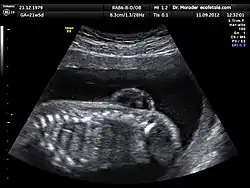

Échographie

L’échographie est la principale et la plus courante des méthodes de diagnostic prénatal. En France, il est ainsi obligatoire de pratiquer trois examens échographiques[9], à 12, 21, puis 33 semaines d’aménorrhée.

Cette technique permet, grâce à l’utilisation d’ultrasons, de voir le bébé par image de synthèse. Elle permet de contrôler l’avancée de la grossesse et détecte un certain nombre de malformations ou de signes avant-coureurs de maladies génétiques. Par exemple, cet examen est l’un des trois composants du « triple test » en vue du dépistage de la trisomie 21, car il permet la mesure de l’épaisseur de la nuque, signe d’appel de cette affection[10].

Le premier examen échographique permet d'exclure des malformations de l'utérus et des tumeurs génitales, de déterminer le nombre de fœtus, de constater la vitalité du/des fœtus, de vérifier l'âge gestationnel en mesurant la longueur vertex-coccyx, de mesurer l'œdème nucal du fœtus et de vérifier la morphologie (tête, thorax, extrémités).

Le 2e examen a pour but principal l'observation de l'anatomie fœtale, afin de montrer directement des malformations fœtales ou de les suspecter à l'aide d'indices indirects. La quantité de liquide amniotique est aussi évaluée, ainsi que la position et la morphologie du placenta[11].

Le 3e examen doit permettre d’évaluer le développement fœtal, le fonctionnement régulier du placenta ainsi que le positionnement exact du fœtus et les problèmes éventuels de cordon ombilical en vue de l’accouchement[12].